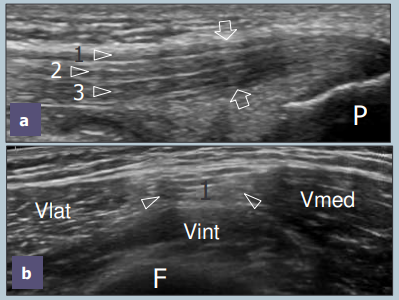

Tendon Quadriceps

Recessus supra-patellaire

Trochlée fémorale